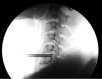

Surgical treatment of the degenerative disc disease has evolved from traditional open spine surgery to minimally invasive spine surgery including endoscopic spine surgery. Constant improvement in the imaging modality especially with introduction of the magnetic resonance imaging, it is possible to identify culprit degenerated disc segment and again with the discography it is possible to diagnose the pain generator and pathological degenerated disc very precisely and its treatment with minimally invasive approach. With improvements in the optics, high resolution camera, light source, high speed burr, irrigation pump etc, minimally invasive spine surgeries can be performed with various endoscopic techniques for lumbar, cervical and thoracic regions. Advantages of endoscopic spine surgeries are less tissue dissection and muscle trauma, reduced blood loss, less damage to the epidural blood supply and consequent epidural fibrosis and scarring, reduced hospital stay, early functional recovery and improvement in the quality of life & better cosmesis. With precise indication, proper diagnosis and good training, the endoscopic spine surgery can give equally good result as open spine surgery. Initially, endoscopic technique was restricted to the lumbar region but now it also can be used for cervical and thoracic disc herniations. Previously endoscopy was used for disc herniations which were contained without migration but now days it is used for highly up and down migrated disc herniations as well. Use of endoscopic technique in lumbar region was restricted to disc herniations but gradually it is also used for spinal canal stenosis and endoscopic assisted fusion surgeries. Endoscopic spine surgery can play important role in the treatment of adolescent disc herniations especially for the persons who engage in the competitive sports and the athletes where less tissue trauma, cosmesis and early functional recovery is desirable. From simple chemonucleolysis to current day endoscopic procedures the history of minimally invasive spine surgery is interesting. Appropriate indications, clear imaging prior to surgery and preplanning are keys to successful outcome. In this article basic procedures of percutaneous endoscopic lumbar discectomy through transforaminal and interlaminar routes, percutaneous endoscopic cervical discectomy, percutaneous endoscopic posterior cervical foraminotomy and percutaneous endoscopic thoracic discectomy are discussed.